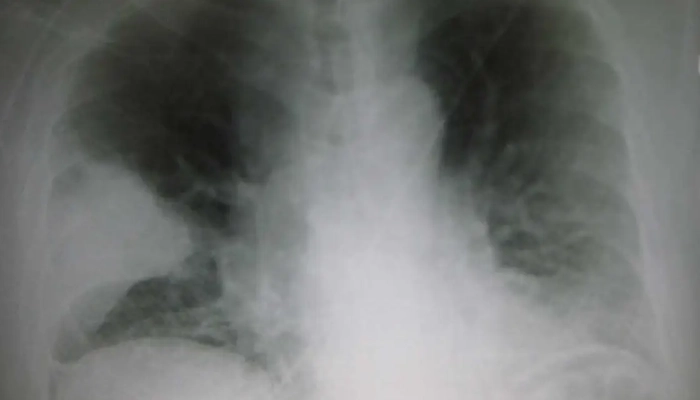

X-quang ngực: hình mờ đậm như bông, thường chiếm một thùy phổi.

X-quang/CT phổi: mảng mờ đồng nhất, có thể thấy phế quản hơi trong vùng đông đặc.

Hình ảnh X-quang phổi trong hội chứng đông đặc

9.2. X-quang phổi có thể chẩn đoán chính xác hội chứng đông đặc không?

X-quang có thể phát hiện vùng đông đặc, nhưng cần kết hợp lâm sàng và các xét nghiệm khác để xác định nguyên nhân.